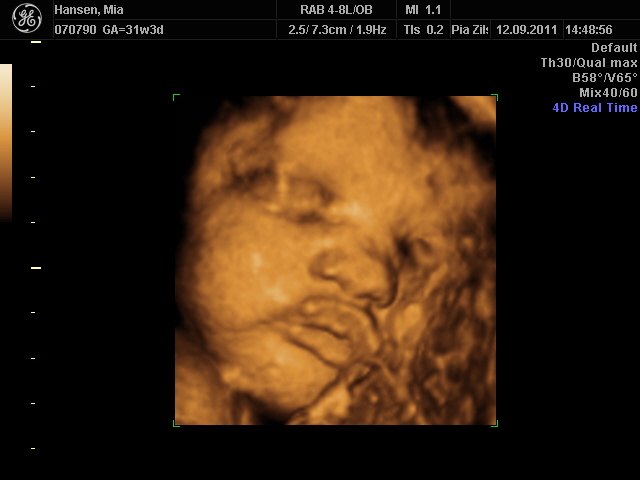

Hun er stadigvæk en rigtig putterøv, men vi fik en masse smil og trut-munde af hende

hun har lange øjenvipper og hår i nakken